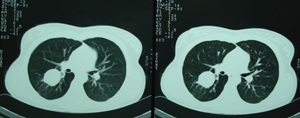

Εικόνα 2

Αξονική τομογραφία του θώρακος που δείχνει μάζα εκ μαλακών μορίων στο μέσο πνευμονικό πεδίο. Η μάζα αυτή έχει ομαλά όρια.